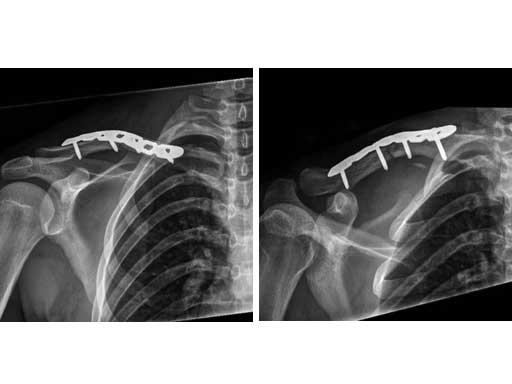

A 21-year old male fell on the right shoulder when playing soccer. He sustained a cavicular shaft fracture type 06 A3 (OTA classification) with dislocation of shaft width and shortening of around 2 cm.

Fig 1ab Preoperative x-rays.

Fig 3ab Immediate postoperative x-rays.